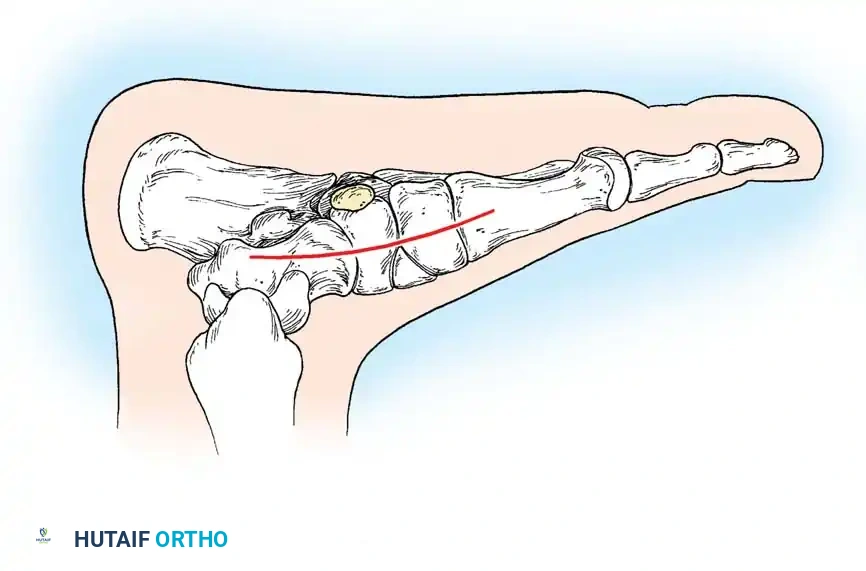

Radiographic Imaging

The 45-degree lateral oblique radiograph is the gold standard for diagnosing a calcaneonavicular coalition. The abnormal bar extends from the anterior process of the calcaneus (just lateral to the anterior facet) dorsally and medially to the lateral/dorsolateral extra-articular surface of the navicular. It typically measures 1 to 2 cm in length and 1 to 1.2 cm in width.

In incomplete coalitions, the adjacent bony margins appear irregular, sclerotic, and indistinct. The talar head may also appear small and underdeveloped.

Radiographic Pearl: The "Pseudocoalition"

In older adolescents and adults, a prominent anterior tuberosity of the calcaneus may overlap the navicular on standard views, creating the illusion of a coalition (pseudocoalition). This must be correlated with clinical subtalar motion and dynamic fluoroscopy or varied-angle oblique radiographs.

While standard anteroposterior and lateral radiographs may show secondary signs (such as the "anteater nose" sign for calcaneonavicular coalitions or the "C-sign" and talar beaking for talocalcaneal coalitions), advanced imaging is often utilized in modern practice.

Advanced Imaging and Anatomical Reference Gallery

The following images illustrate various presentations, surgical exposures, and advanced imaging modalities (including CT and MRI correlates) utilized in the comprehensive evaluation and treatment of rigid pes planus and tarsal coalitions: